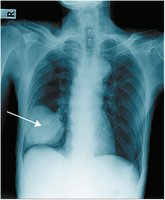

Atelectasis refers to the collapse of part or all of a lung, resulting in reduced gas exchange and visible as a hazy area on chest x-ray.

Pneumonia

Pneumonia is an infection of the lung tissue, visible on x-ray as a dense, gray-white area. It can be caused by bacteria, viruses, or fungi.

Chest x-rays are commonly used to visualize lung structure and diagnose conditions such as pneumonia, atelectasis, and tumors.